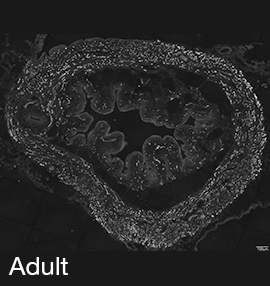

Figure 2A: Structure of cholinergic motor axons in the bladder (adult mouse).

Examples of cholinergic axons immunolabelled for vesicular acetylcholine transporter (VAChT; Slc18a3) in cryosections of mouse bladder at E16 (See GUDMAP RID N-FKKE), P2 (See GUDMAP RID N-FN0P) and adult (See GUDMAP RID N-FNFP).